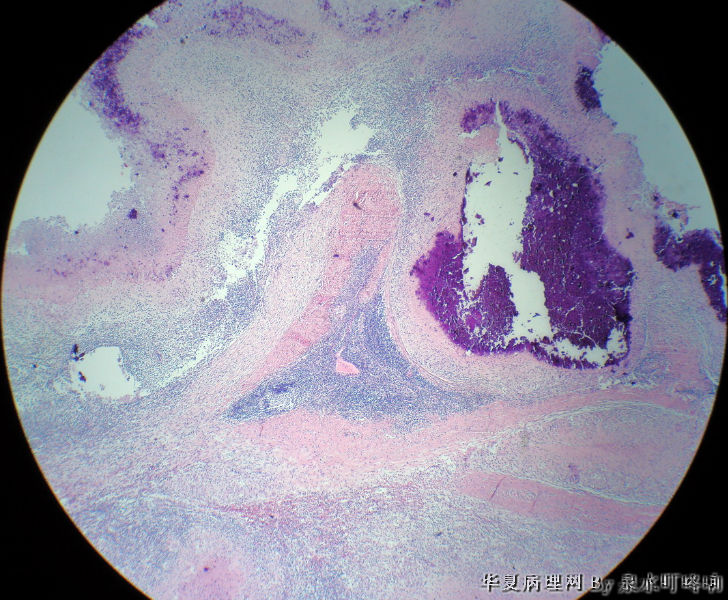

左腋窝肿物

• 左腋窝肿物图1

图1

女,3岁,主因左腋窝肿物半年,术中见为肿大淋巴结,淋巴结内有脓液及坏死组织。

大体:灰红色组织一块,大小约4.6×3.5×2厘米,切面可见两个囊性区域,内容乳白色浓稠液体。

肉芽肿性炎(建议做抗酸染色,除外结核)

是淋巴结吧,淋巴结肉芽肿性炎伴坏死,建议做抗酸染色。

肉芽肿性炎,考虑结核伴钙化。